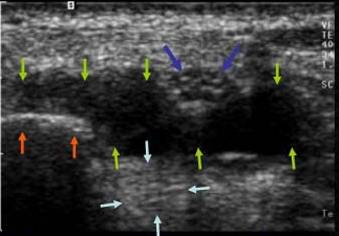

Se traduce ecografic printr-o ingrosare fuziforma a tendonului, centrata de o placa de dezorganizare a fibrelor de colagen care ia un aspect de placa hipoecogena nodulara pe sectiunile axiale si fuziforma pe sectiunile sagitale. Acest nodul se situeaza pe fata profunda a tendonului respectand fibrele superficiale. Prezenta unei vascularizatii de neoformatie reactionala in jurul si pe fata posterioara a nodulului indica cicatrizarea leziunii.

Clinic – punct dureros in mijlocul patelei Ecografic, insertia proximala a tendonului patelar este semnul unui epansament centrat pe un nodul hipo ecogen cu respectarea fibrelor superficiale si prezenta unei hiper vascularizatii periferice la doppler color.